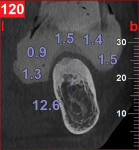

A CBCT study shows hard tissues and the shadow of soft tissues as long as they are surrounded by hard tissue. The pulpal tissue of the teeth is not visible, but the outline of the pulp chamber is visible. The mandibular nerve is not visible, but the cortical bone surrounding it does appear on the CBCT, making it possible to deduce where the mandibular nerve is expected to be. The proposed visualization technique allows very strong contrast to create a negative, much like the just-discussed image of the mandibular nerve. The concept is rather simple; VPS impression material can be radiopaque, but not all materials are radiopaque to the same extent, and some are not radiopaque at all (Figure 2). The patient wears a VPS impression during the CBCT exposure (Figure 3 and Figure 4). This can be the actual impression, or a dedicated impression made from a diagnostic cast (Figure 5). This simple technique shows a very distinct space, which is visible between the VPS material and the bone (Figure 6 and Figure 7). For the purpose of the 3D Click Guide fabrication, this space would otherwise be measured with the bone-sounding technique, as discussed in Part 1 of this series. Because the surface of the VPS impression visible in the CBCT image is exactly similar to the surface of the cast, the two can be exactly superimposed. Within the CBCT software, simple measurements can be made. Those measurements are made at the same locations as those used when bone sounding. Those measurements are then transferred to the cast. Additional information—eg, location of the mandibular canal—can be extrapolated and drawn as needed (Figure 8 and Figure 9).

An 80-year-old woman, who presented with a missing lower molar, requested an implant-supported replacement. Advanced periodontal bone loss at site No. 19 resulted in considerable resorption of the alveolar ridge after healing. Although simple bone sounding is the preferred data-gathering technique for the author, in this case, there was insufficient information available to safely perform an osteotomy. The decision was made to gather additional information with a CBCT study.

The cast was sectioned 4 mm distal of tooth No. 20. The data from the corresponding cross-sectional cut were transferred to the cast. The ideal buccolingual axis was drawn onto the cast, based on a screw access hole in the central fossa of the future crown. A small hole was drilled at the desired location of the shoulder of the implant. The pin of the Bucco Lingual Positioner (BLP) was placed in the hole, and the central groove of the BLP was lined up with the drawn implant axis. A drop of fast-setting cyano-acrylate glue was applied to lock the BLP in place (Figure 11). The opposing part of the cast was adjusted and the cast was reassembled into the Accu-trac tray. At this point, the buccolingual axis and the top of the implant were irreversibly set, and the mesiodistal could be determined without the risk of making inadvertent changes in the buccolingual plane. The correction slot in the crossbar of the wing assembly fits snugly over the top of the BLP, allowing mesiodistal rotation and mesiodistal translation (Figure 12). Once the correct mesiodistal position was selected, the wings were irreversibly connected to the vacuformed carrier by means of ortho-acrylic (Orthoresin, DENTSPLY International, www.dentsply.com); then the cross-sectional bar was removed, allowing placement of a rotation block. The surgical guide was placed in the mouth and a periapical radiograph was exposed (Figure 13). Note that if the buccal and lingual wings overlap and appear to be one, the radiograph has been taken exactly perpendicular to the ridge, allowing a decision to be made because the image is of acceptable diagnostic quality. In this case, the trajectory was as desired, and the 0º rotation block was selected, as there was no need for rotation adjustments by means of the 3º or 7º rotation blocks (Figure 14). The surgical guide was sterilized in a cold sterilizing solution and the surgery was performed per the manufacturer’s drilling protocol. A 8.5-mm x 4.3-mm implant (NobelActive™ 4.3 x 10 mm, Nobel Biocare, www.nobelbiocare.com) was placed as planned (Figure 15).